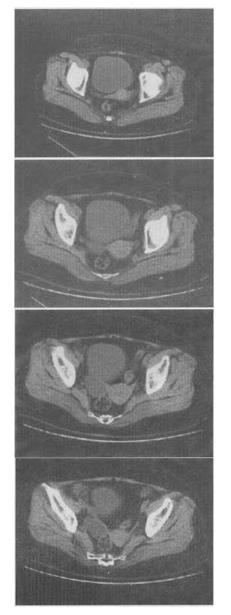

女,27岁,体检时B超发现右侧附件区囊性占位性病变,CT检查如图,下列说法错误的是()。

A、病灶来源于右侧卵巢

B、病灶边界清晰

C、病灶为单房,壁薄,无分隔

D、考虑为卵巢浆液性囊腺瘤

E、考虑为卵巢囊肿

D